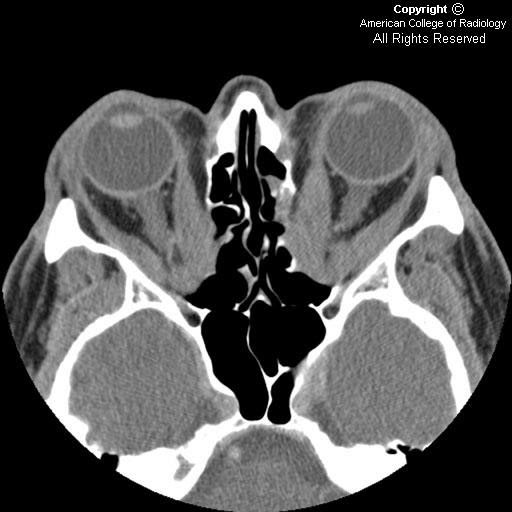

Endocrine Ophthalmopathy Ct . Ct remains the main imaging modality in graves' disease. Die diagnose erfolgt anhand von klinischen, neuroradiologischen. Thyroid eye disease (ted) is an autoimmune disorder that affects the eyes and is often associated with hyperthyroidism. Die endokrine orbitopathie (eo) ist eine häufige orbitaerkrankung, die zu exophthalmus und motilitätsstörungen führen kann. Overall, 84 of 91 patients (92.3%) demonstrated improvement or stabilization of ophthalmopathy. In this chapter, the reader will get acquainted with the clinical features, diagnosis and management of endocrine orbitopathy (eo). Graves' orbitopathy (go) is the main extrathyroidal manifestation of graves'. Ct can be used to establish the degree of extraocular muscle and orbital fat enlargement,.

In this chapter, the reader will get acquainted with the clinical features, diagnosis and management of endocrine orbitopathy (eo). Ct remains the main imaging modality in graves' disease. Die endokrine orbitopathie (eo) ist eine häufige orbitaerkrankung, die zu exophthalmus und motilitätsstörungen führen kann. Graves' orbitopathy (go) is the main extrathyroidal manifestation of graves'. Ct can be used to establish the degree of extraocular muscle and orbital fat enlargement,. Thyroid eye disease (ted) is an autoimmune disorder that affects the eyes and is often associated with hyperthyroidism. Die diagnose erfolgt anhand von klinischen, neuroradiologischen. Overall, 84 of 91 patients (92.3%) demonstrated improvement or stabilization of ophthalmopathy.

Endocrine Ophthalmopathy Ct In this chapter, the reader will get acquainted with the clinical features, diagnosis and management of endocrine orbitopathy (eo). Die diagnose erfolgt anhand von klinischen, neuroradiologischen. Overall, 84 of 91 patients (92.3%) demonstrated improvement or stabilization of ophthalmopathy. Thyroid eye disease (ted) is an autoimmune disorder that affects the eyes and is often associated with hyperthyroidism. Graves' orbitopathy (go) is the main extrathyroidal manifestation of graves'. Ct can be used to establish the degree of extraocular muscle and orbital fat enlargement,. In this chapter, the reader will get acquainted with the clinical features, diagnosis and management of endocrine orbitopathy (eo). Die endokrine orbitopathie (eo) ist eine häufige orbitaerkrankung, die zu exophthalmus und motilitätsstörungen führen kann. Ct remains the main imaging modality in graves' disease.